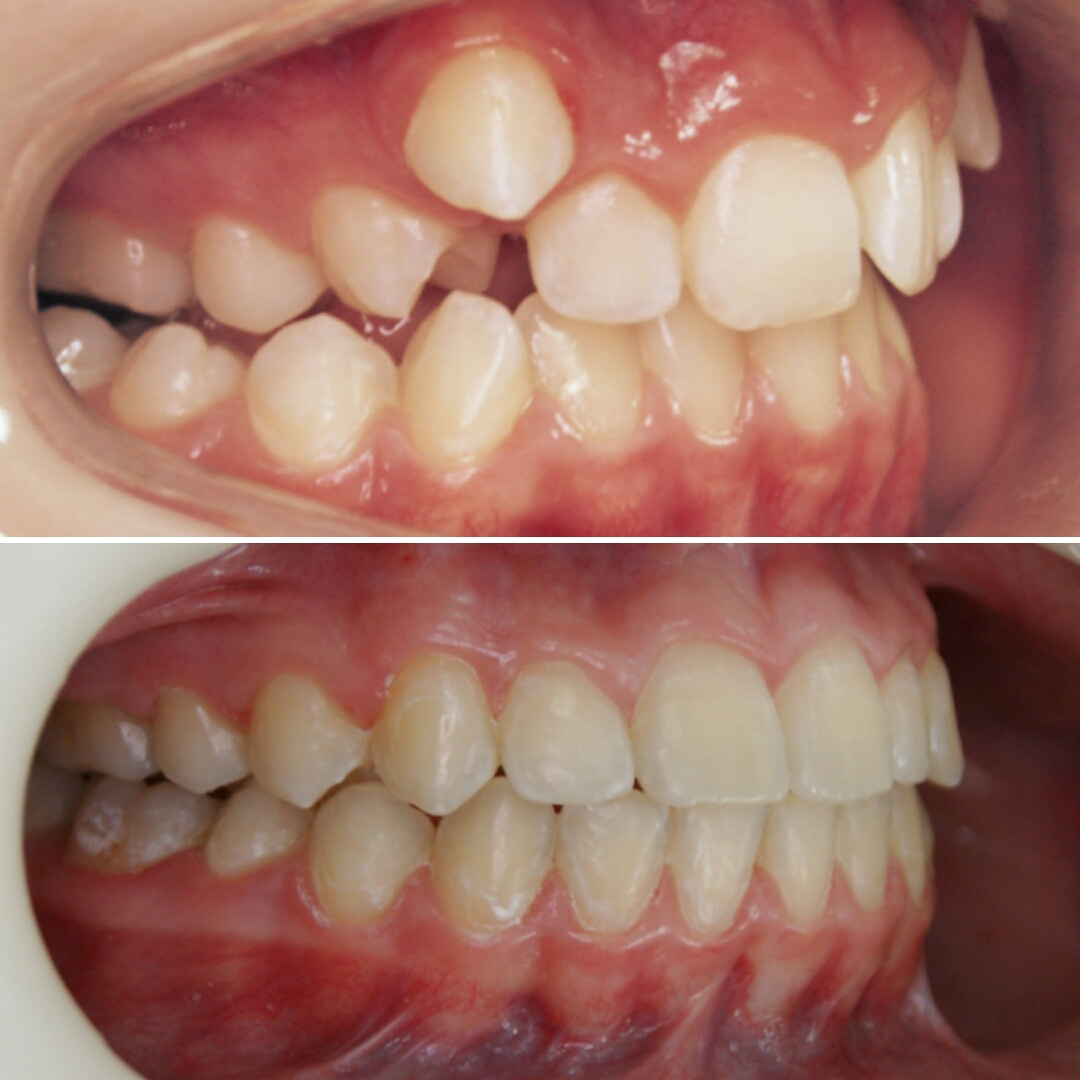

Эта фраза знакома многим ответственным родителям, которые привели на приём к ОРТОДОНТУ своего ребёнка в 5-10 лет, заподозрив проблему или понимая, что места постоянным зубам откровенно не хватает! Горькая правда в том, что брекеты - не волшебное средство от всех проблем, они "расставляют" зубы внутри сформированого объёма челюсти, но никак не влияют на её рост. Родители ждут, а тем временем драгоценное время, когда ребёнок растёт, уходит... Во взрослом возрасте приходится удалять здоровые зубы или прибегать к ортогнатической хирургической операции. 📸 На фото узкая нижняя челюсть, места постоянным зубам нет, боковые резцы прорезываются "вторым рядом".

✅ Помогаем с помощью расширяющей дуги, пружины и зацепных элементов, которые зафиксированы на МОЛОЧНЫЕ зубы